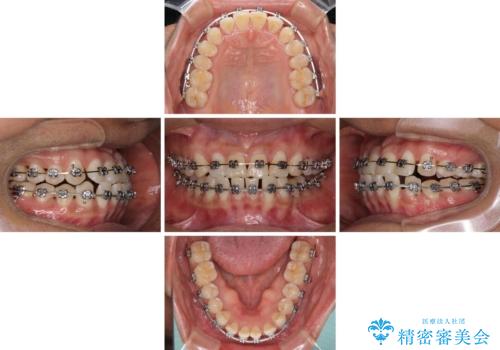

- 矯正装置

- メタルブラケット

咬合力が強く、反対咬合の改善に時間がかかりましたが、その後はスムーズに進めることができました。

途中、妊娠と出産があり、治療が中断したため、治療期間は延びましたが、出産も矯正治療も無事に終えることができました。